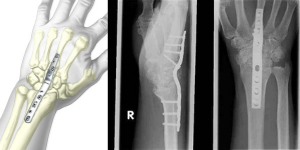

Hàn khớp

Nếu cử động là nguồn gốc gây ra cơn đau của bạn, bác sĩ có thể khuyên bạn nên hàn khớp. Hàn khớp là một phẫu thuật kết hợp các xương thành một khối. Ý tưởng cơ bản là hợp nhất các xương lại với nhau để chúng lành lại thành một xương vững chắc duy nhất. Lý thuyết đằng sau sự hợp nhất là, nếu xương bị đau không di chuyển, chúng sẽ không bị đau.

Trong quá trình phẫu thuật, bác sĩ sẽ loại bỏ sụn bị hư hỏng và sau đó ghép xương xốp vào giữa các xương, sử dụng vít rỗng hoặc nẹp vít để cố định. Theo thời gian, các xương hàn với nhau được kết nối thành một khối - tương tự như cách các đầu xương bị gãy liền lại với nhau.

Trong một số trường hợp, bác sĩ có thể thực hiện hàn khớp một phần, trong đó chỉ một số xương cổ tay được hàn với nhau. Điều này giải quyết các bề mặt khớp bị tổn thương, nhưng vẫn giữ nguyên các khớp khỏe mạnh để duy trì một số vận động của cổ tay.

Tuy nhiên, nếu tình trạng viêm khớp của bạn lan rộng, có thể cần phải hàn khớp toàn bộ cổ tay. Trong phẫu thuật này, tất cả các xương cổ tay được hàn khớp với nhau, cùng với xương quay (một trong các xương ở cẳng tay). Mặc dù tất cả vận động của cổ tay được loại bỏ hoàn toàn, nhưng vận động quay của cẳng tay và ngón tay / ngón cái thường được giữ nguyên.